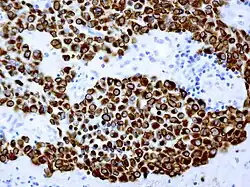

Als Crooke-Zellen werden hyalinisierte basophile Zellen der Adenohypophyse bezeichnet, die von dem englischen Endokrinologen Arthur Carleton Crooke (1905–1990) erstmals beschrieben wurden.[1] Charakteristisch ist auch die ringförmige Einlagerung von Zytokeratinen.[2][3]

Crooke-Zellen stellen sekundäre regressive Veränderungen ACTH-produzierender Zellen der Adenohypophyse bei Hyperkortisolismus dar und werden typischerweise beim Cushing-Syndrom, aber auch nach medikamentöser Kortisongabe im nichtneoplastischen adenohypophysealen Gewebe beobachtet.

Hiervon abzugrenzen ist das sogenannte Crooke-Zelladenom, eine seltene Variante des ACTH-Zelladenoms, dessen Tumorzellen die Morphologie von Crooke-Zellen aufweisen.[2]